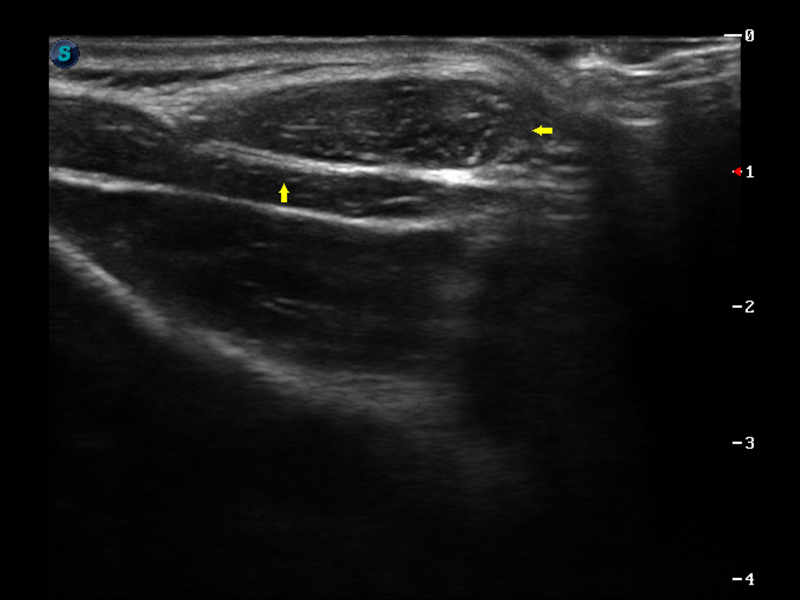

S9便携式彩色多普勒超声诊断仪是玖鼎集团研发的高端便携彩超设备,外观设计新颖、产品性能卓越。S9在便携超声领域采用了突破传统的触摸屏交互设计,并以先进的软件硬件技术和设计理念,为您带来清晰的图像质量、稳定的工作性能和便捷的操作体验。

μ-Scan微米成像

脉冲反相谐波成像